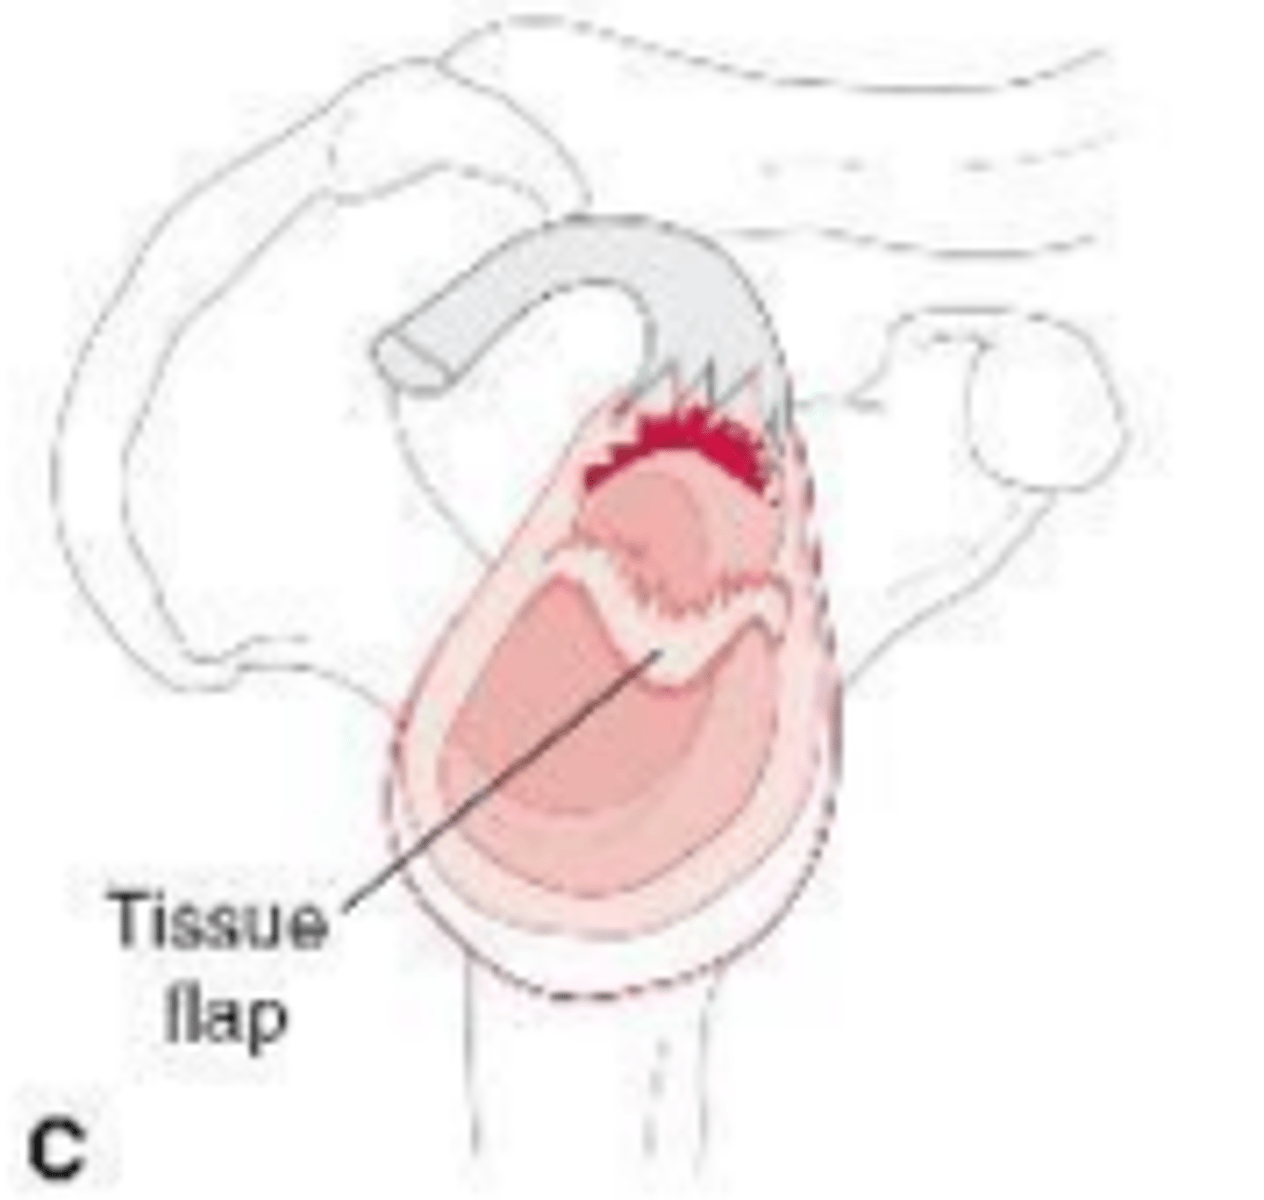

Tissue flap-bucket handle tear of labrum and stable labrum/biceps complex on the glenoid

What does the image show?